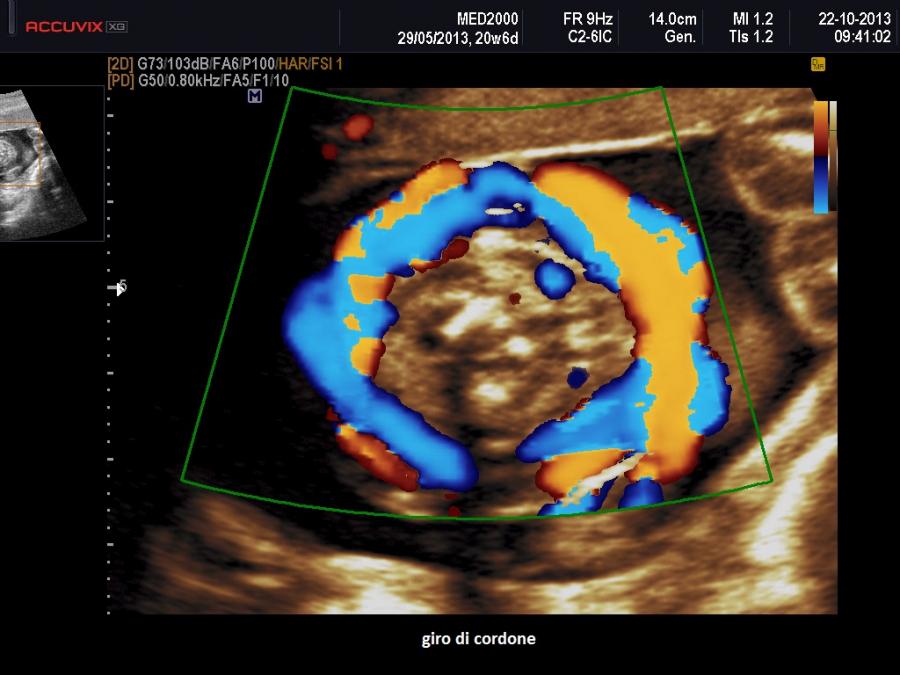

I giri di cordone intorno al collo sono molto frequenti, con una incidenza di circa il 15-30% di tutte le gravidanze e non rivestono alcun fattore di esito avverso; i giri multipli hanno una incidenza del 2-3,8%. L'influenza sull'outcone feto-neonatale dei giri di cordone è praticamente nulla per i giri singoli, mentre quelli multipli possono peggiorarlo. Il rischio aumenta in presenza di oligoidramnios, di riduzione dei movimenti attivi fetali, di alterazione del tracciato cardiotocografico. E' molto dibattuta la comunicazione di tale condizione alla paziente; ciò può avere delle ricadute psicologiche negative, generando ansie e tensione che a loro volta possono condizionare negativamente la condotta di chi dovrà assistere il travaglio e il parto ( tratto da www.sieog.it).